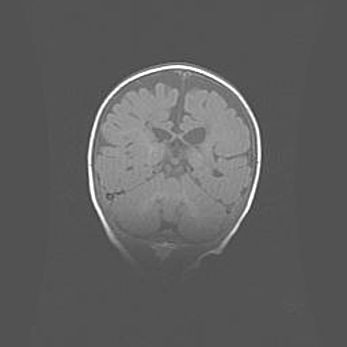

Церебральная ишемия II.

Возраст: 5 дней

Вес: 3400 г

Пол: женский

Окружность головы: 35 см

Срок гестации: 39 недель

Церебральная ишемия – это заболевание, характеризующееся недостаточностью (гипоксией) либо полным прекращением (аноксией) снабжения мозга кислородом по причине закупорки одного или нескольких сосудов. Это приводит к  что метаболическим расстройствам различной степени тяжести в тканях головного мозга, развитию коагуляционных некрозов и гибели нейронов.